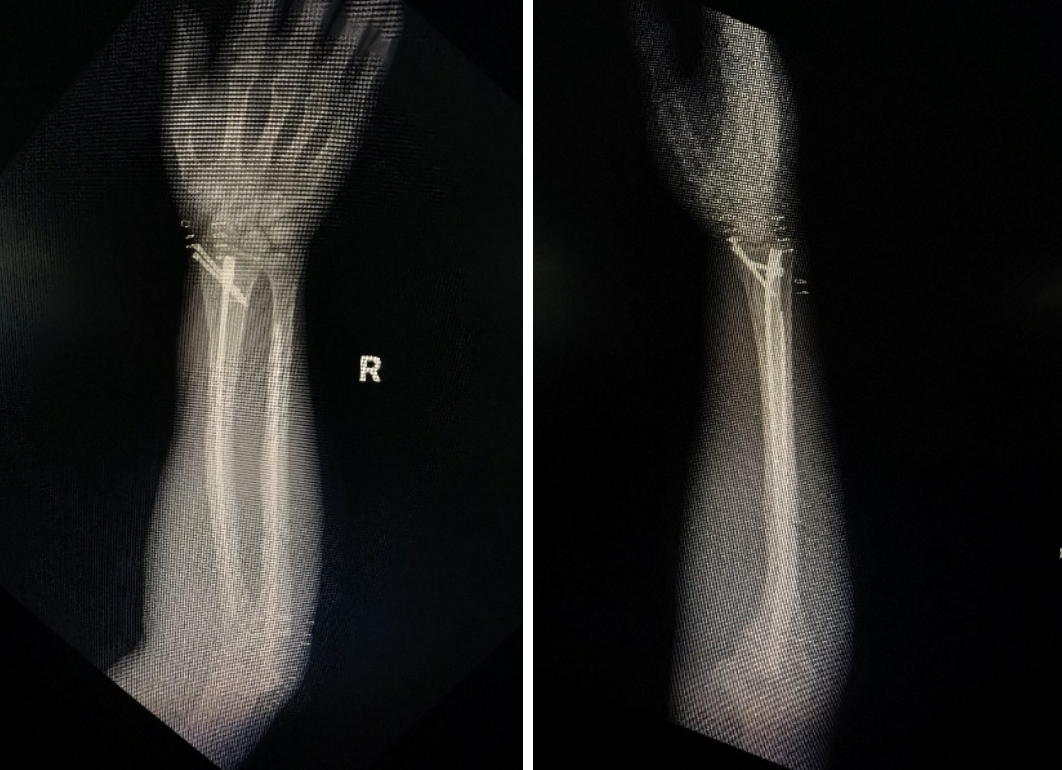

手术在C型臂X光机精准透视下开展,手术团队严格遵循微创操作规范,通过手法闭合复位,将带锁髓内钉精准植入尺桡骨髓腔,交锁锁钉固定,实现骨折端的稳定复位与加压固定。整个手术过程顺利,术中出血量少,患者生命体征平稳。术后,医护团队在加速康复外科(ERAS)理念指导下,为患者制定个性化康复计划,指导其逐步开展肢体功能锻炼。术后,患者前臂肿胀明显消退,软组织条件明显改善,疼痛症状显著缓解,恢复状况远超预期。

术后